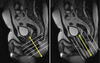

17

Abdome: cólon e reto

A __________ (doença de Crohn/retocolite ulcerativa) envolve todas as camadas intestinais, podendo resultar em fístulas.

A __________(doença de Crohn/retocolite ulcerativa) tem inflamação confinada à mucosa e submucosa do intestino grosso.

A

Doença de Crohn; retocolite ulcerativa.

Fístula entre alças de intestino delgado em paciente com Crohn; a alta resolução de partes moles da RM ajuda a delimitar melhor fístulas pequenas.